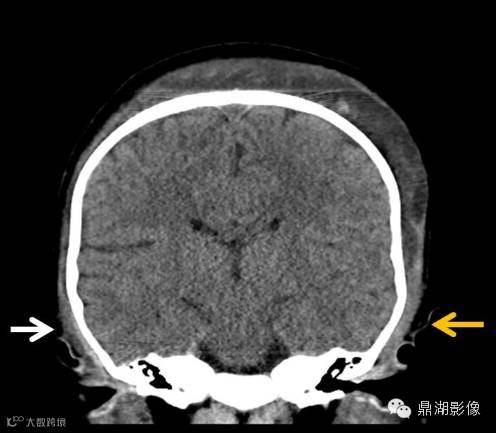

帽状腱膜下血肿多见于新生儿产伤。阴道自然顺产帽状腱膜下血肿的发生率为 0.4‰ ,负压吸引助产的发生率为 5.9‰ ,头皮牵引助产可损伤头皮与静脉窦之间的导静脉,从而导致帽状腱膜下血肿的发生。帽状腱膜下间隙的范围从前方的眶上缘,向后延伸到颈部后方,两侧到耳廓外侧的水平。帽状腱膜下间隙不受颅缝限制,因此大量出血可以在此聚集。血容量的大量丢失可导致休克及凝血障碍,死亡率为 14%。

帽状腱膜下出血是颅骨骨膜与帽状腱膜之间的疏松结缔组织出血。大量出血可聚积于帽状腱膜下间隙,使新生儿和儿童潜在的死亡风险增高。梳头时过于用力可致儿童帽状腱膜下出血,早期病因识别可以避免不必要的临床评价和干预,并排除虐童的可能性。